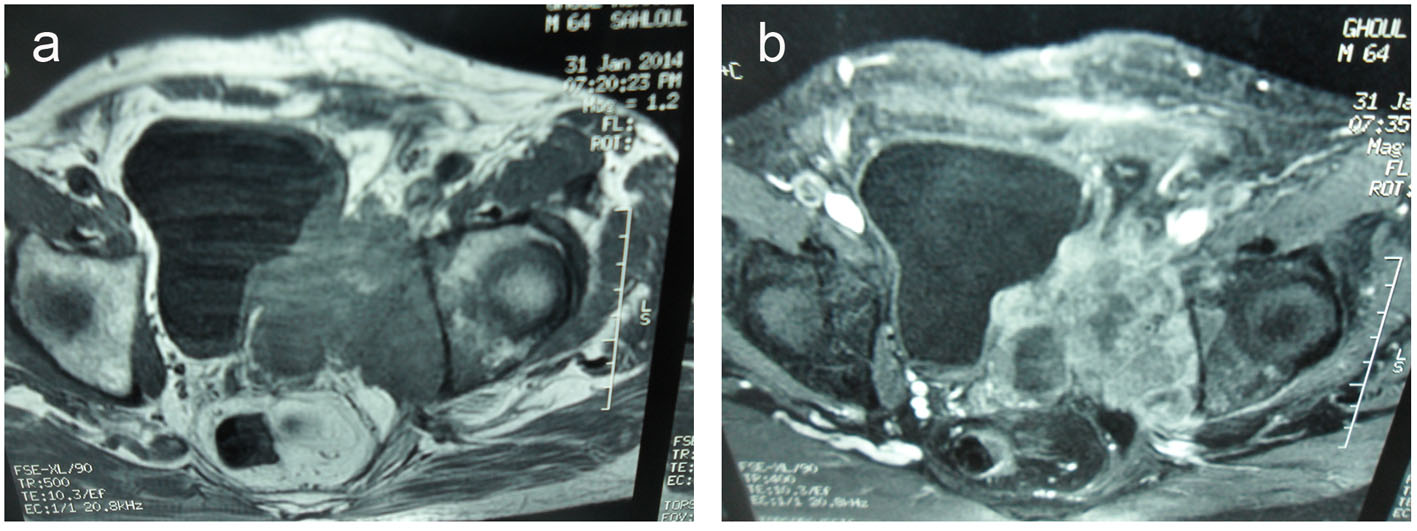

A pelvic magnetic resonance imaging (MRI) was performed to further characterize this mass.

It demonstrated a 10 × 9 × 12 cm solid, poorly defined and heterogeneous mass on the left seminal vesicle wall. The mass was hypo-signal in T1 sequences and hyper-signal in T2 sequences compared to the muscle and has an important local invasion. The mass invades the posterior and lateral bladder wall, the prostate base, the internal obdurate and serratus muscle and the hip bone, and the external and internal iliac lymph nodes were also invaded (Fig. 3).

![]() Click for large image | Figure 3. (a) Transverse T2-weighted MR images and transverse T1-weighted MR images (b). A 10 × 9 × 12 cm solid and heterogeneous mass in the left seminal vesicle wall. The mass was hypointense in T1-weighted and hyperintense in T2-weighted MR images compared to the muscle. The mass invades the posterolateral bladder wall, the prostate base, the internal obturator and serratus muscles and the hip bone. |